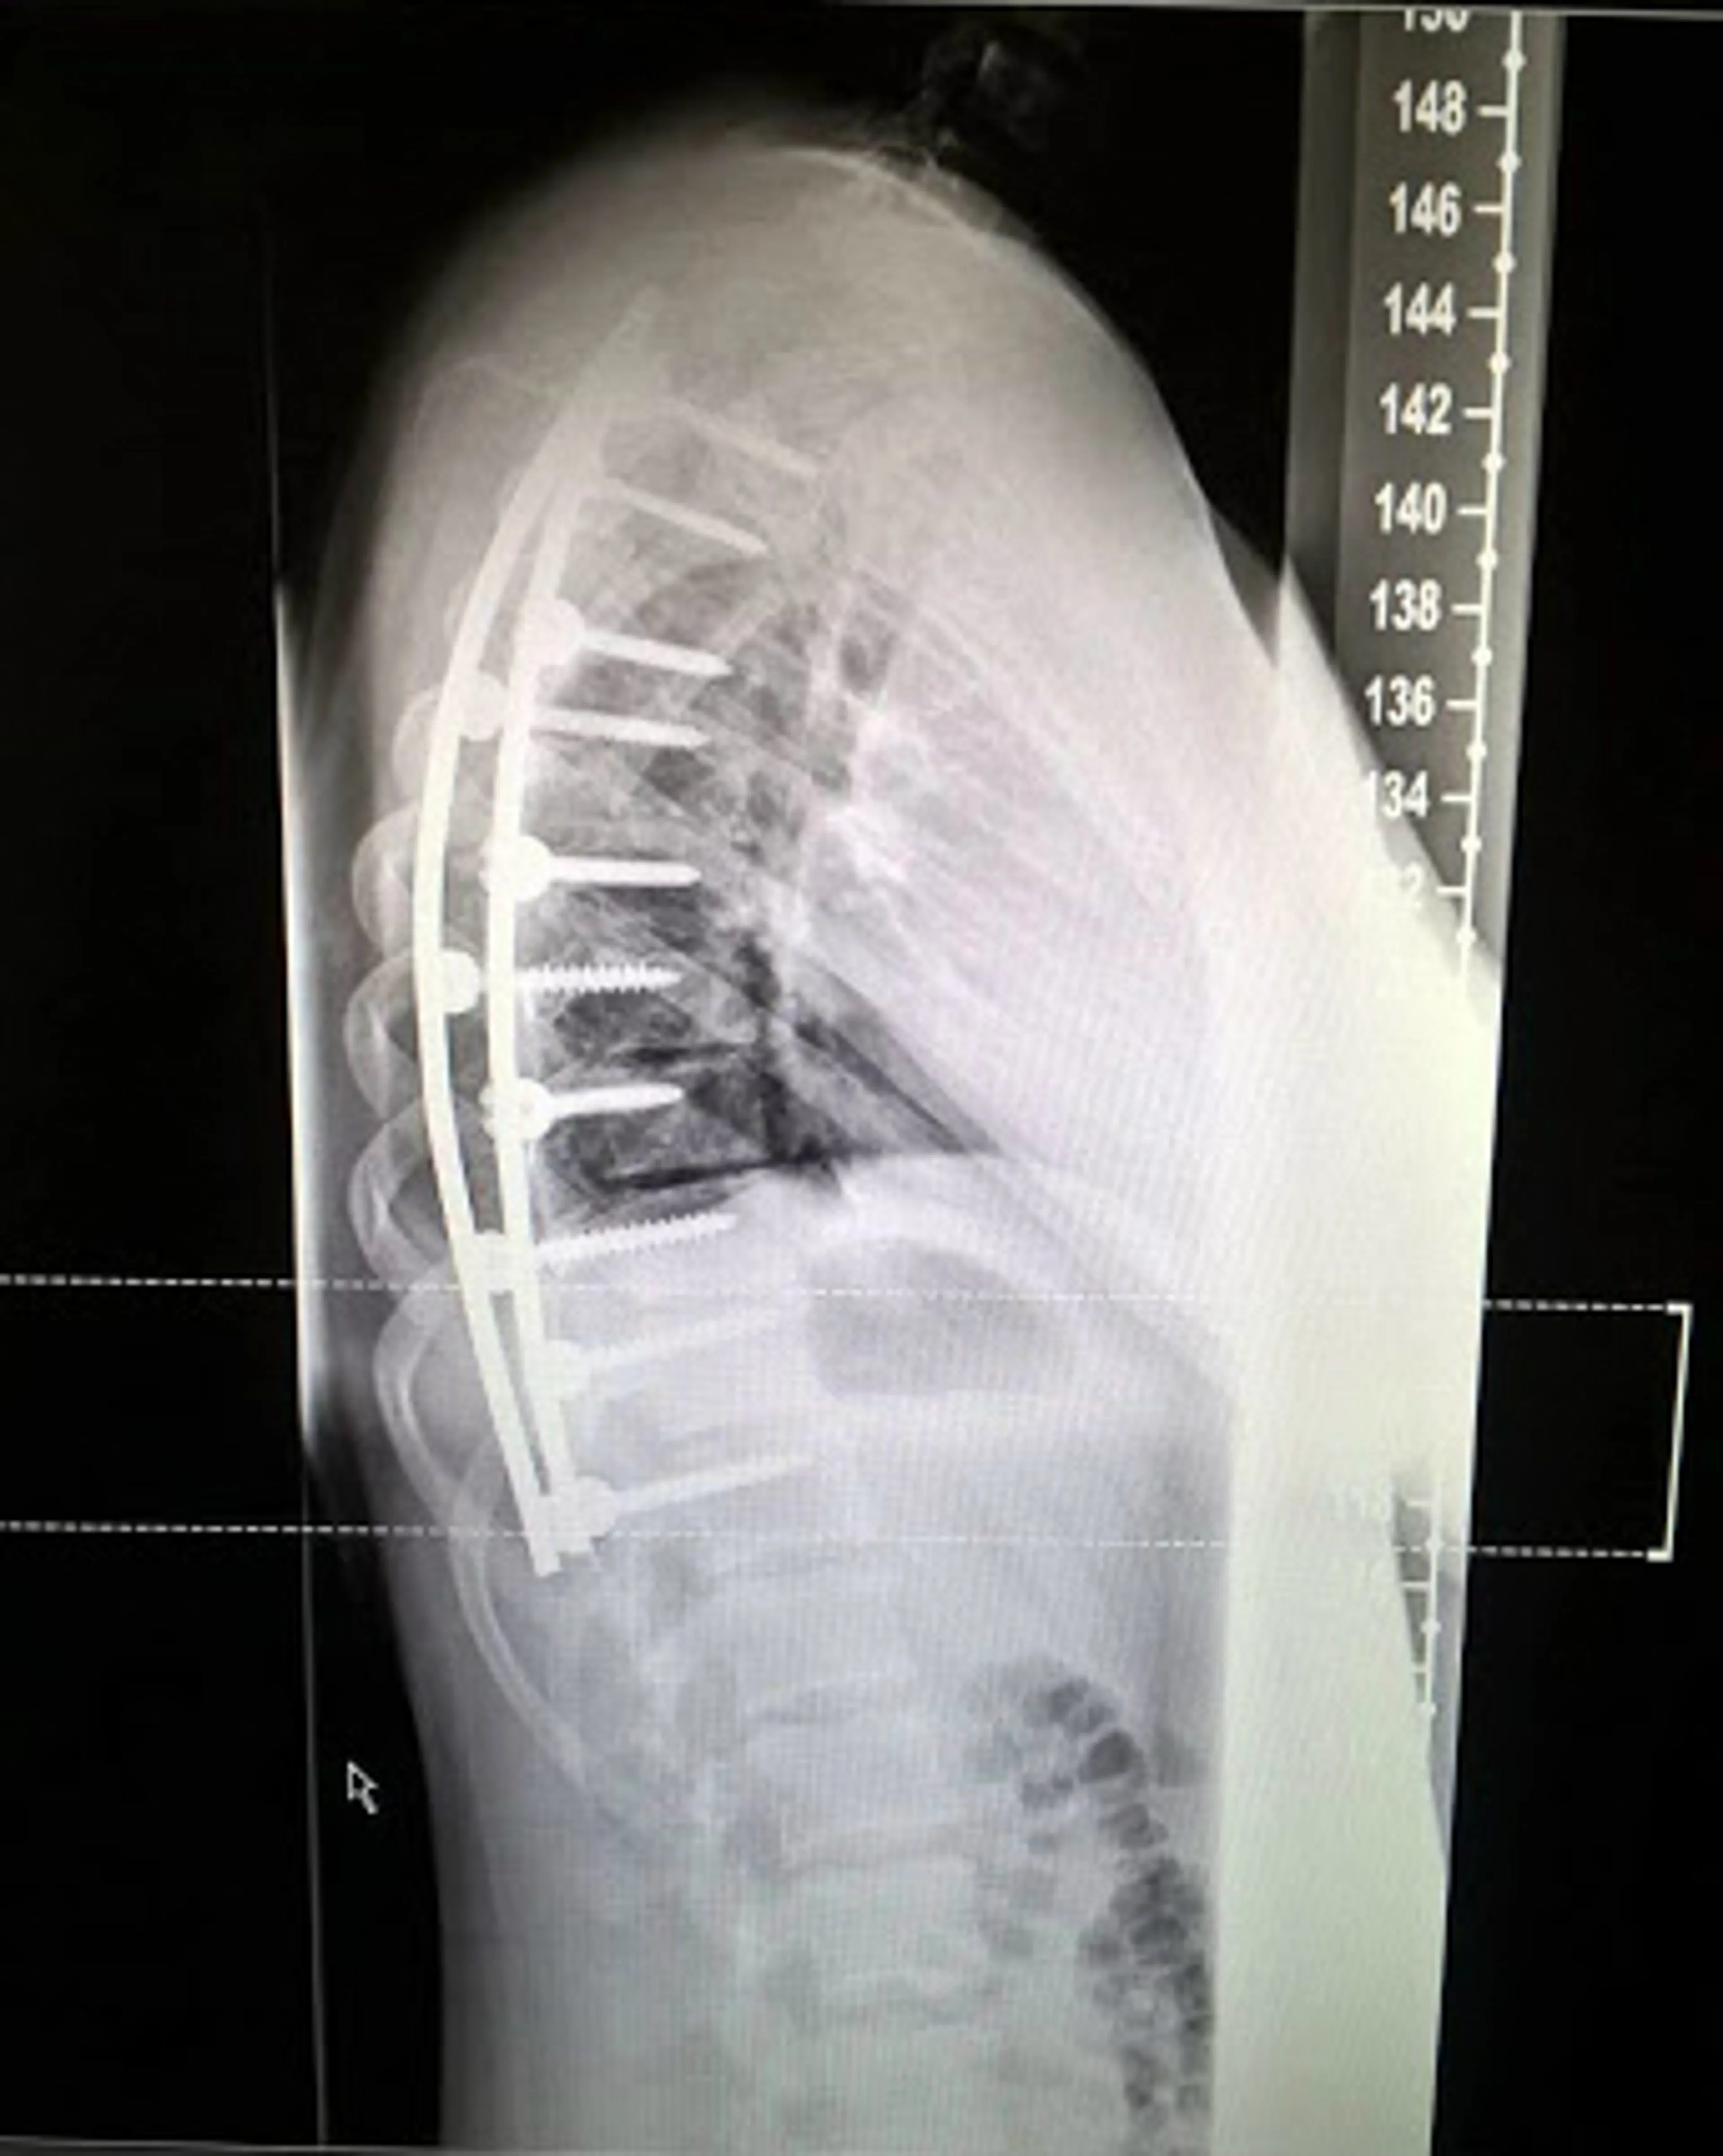

Bij de dokter moest ik een buktest doen. Er wordt dan gekeken of er ongelijkheden zijn in de stand van je ribbenkast. Bij mij stond de rechterhelft veel hoger, omdat mijn ribbenkast gedraaid stond, vanwege de bocht in mijn wervelkolom. Het was voor de huisarts direct duidelijk dat ik een scoliose had. Ik had geen idee wat een scoliose was, dus dat heeft ze allemaal uitgelegd. De huisarts stuurde mij toen door naar de orthopeed. Daar heb ik een röntgenfoto laten maken. De orthopeed mat een bocht van veertig graden. Mijn scoliose is ontstaan tijdens de groeispurt in de puberteit."

"De maanden, weken en zelfs dagen voor mijn operatie was ik dan ook helemaal niet zenuwachtig. Ik had er zelfs zin in! Ik vertrouwde volledig op God. De operatie verliep goed en ze hebben de bocht kunnen rechttrekken tot dertien graden. Rechter trekken dan dat was te risicovol, vanwege alle zenuwen in je ruggengraat en de kans op een dwarslaesie.